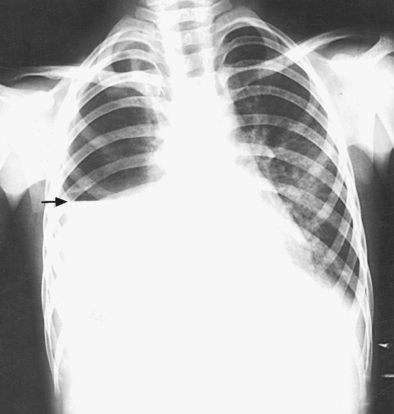

When pneumothorax (gas or air in the pleural cavity) is suspected, one exposure is often made at the end of full inspiration and another at the end of full expiration to show small amounts of free air in the pleural cavity that might be obscured on the inspiration exposure (Figs. 10-16 and 10-17). Inspiration and expiration radiographs are also used to show the movement of the diaphragm, the occasional presence of a foreign body, and atelectasis (absence of air).

For certain conditions, such as pneumothorax and the presence of a foreign body, radiographs are sometimes made at the end of full inspiration and expiration (Figs. 10-29 to 10-31). Pneumothorax is shown more clearly on expiration because collapse of the lung is accentuated.

Structures shown: AP or PA projection obtained using the lateral decubitus position shows the change in fluid position and reveals any previously obscured pulmonary areas or, in the case of suspected pneumothorax, the presence of any free air (Figs. 10-62 to 10-64).